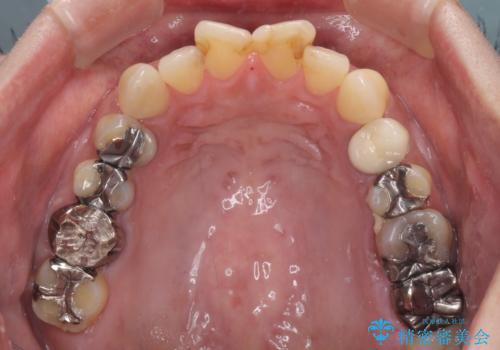

- 何度もコンポジットレジンによる修復を繰り返した結果、冷たいものがしみるようになってしまったとのことで来院された患者様です。

前歯2本が捻れている形態も気になるとのことであったので、虫歯の治療を兼ねて、オールセラミッククラウンにて補綴治療を行うこととしました。

2本とも治療前の歯髄の状態は正常でしたが、補綴治療により歯を大きく削ることになるため、歯髄が炎症を起こすリスクがあることを了解いただきました。